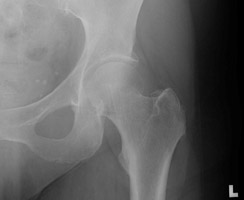

- Click on the image for a larger versionDAP radiograph of the right hip. This shows a Garden III fracture of the proximal femur.